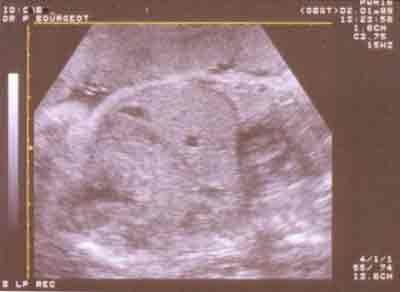

Coupe sagittale en fin de grossesse montrant le diaphragme : bande arciforme anéchogène